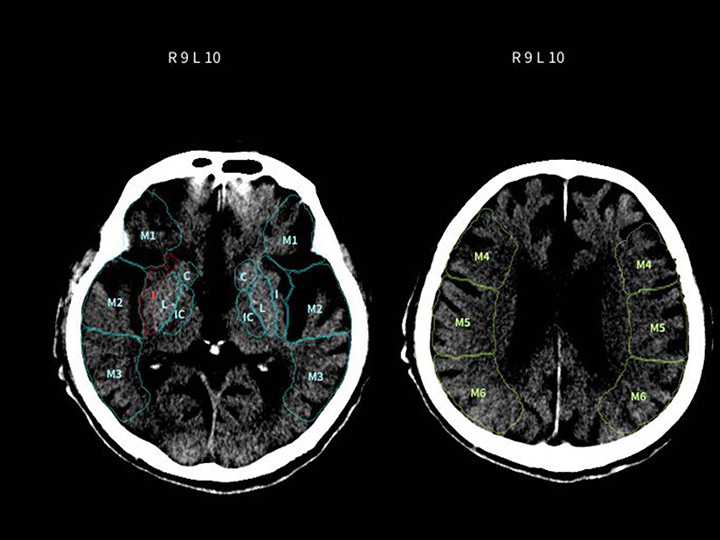

導入の相談はこちら頭部CT×高吸収/低吸収域

DoctorNET Heuron CTS

頭部非造影CT画像から、画像内の高吸収域または低吸収域を検出します

- 救急現場での読影補助として

- 頭部が専門ではない先生の補助として

- 販売名

- 頭部CT画像解析AIエンジン DoctorNet Heuron CTS

- 医療機器承認番号

- 307AGBZX00052000

- 一般的名称

- 汎用画像診断装置ワークステーション用プログラム

- クラス分類

- クラスII

- 承認年月日

- 令和7年10月2日

- 種別

- プログラム(01) 疾病診断用プログラム